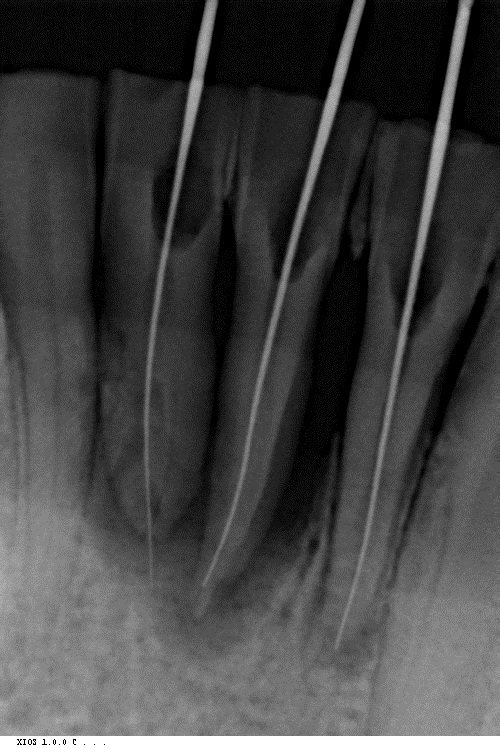

Здравствуйте! Хотелось бы получить общую консультацию по снимку. Очень плохие зубы с детства, постоянно беспокоят и просто разрушаются. Хотелось бы понять — есть возможность спасти хотя бы корни большинства зубов? Существуют ли вообще очень серьезные проблемы?

Добрый день. Особых проблем я не вижу, уважаемый пациент. 4.7 зуб необходимо тщательно осмотреть на предмет пригодных тканей для последующего восстановления вкладкой и коронкой, на 4.6 также есть воспаление на верхушке корня, все также необходимо пролечить затем изготовить культевую вкладку и коронку, 3.6 необходимо перелечить, плохая некачественная пломбировка, а также большая по площади пломба, при неблагоприятном исходе может привести к сколу стенки, что в последствии также к потере зуба, 2.6 скорее всего удалится, но еще раз стоит сделать ревизию, 1.6 необходимо перелечить.